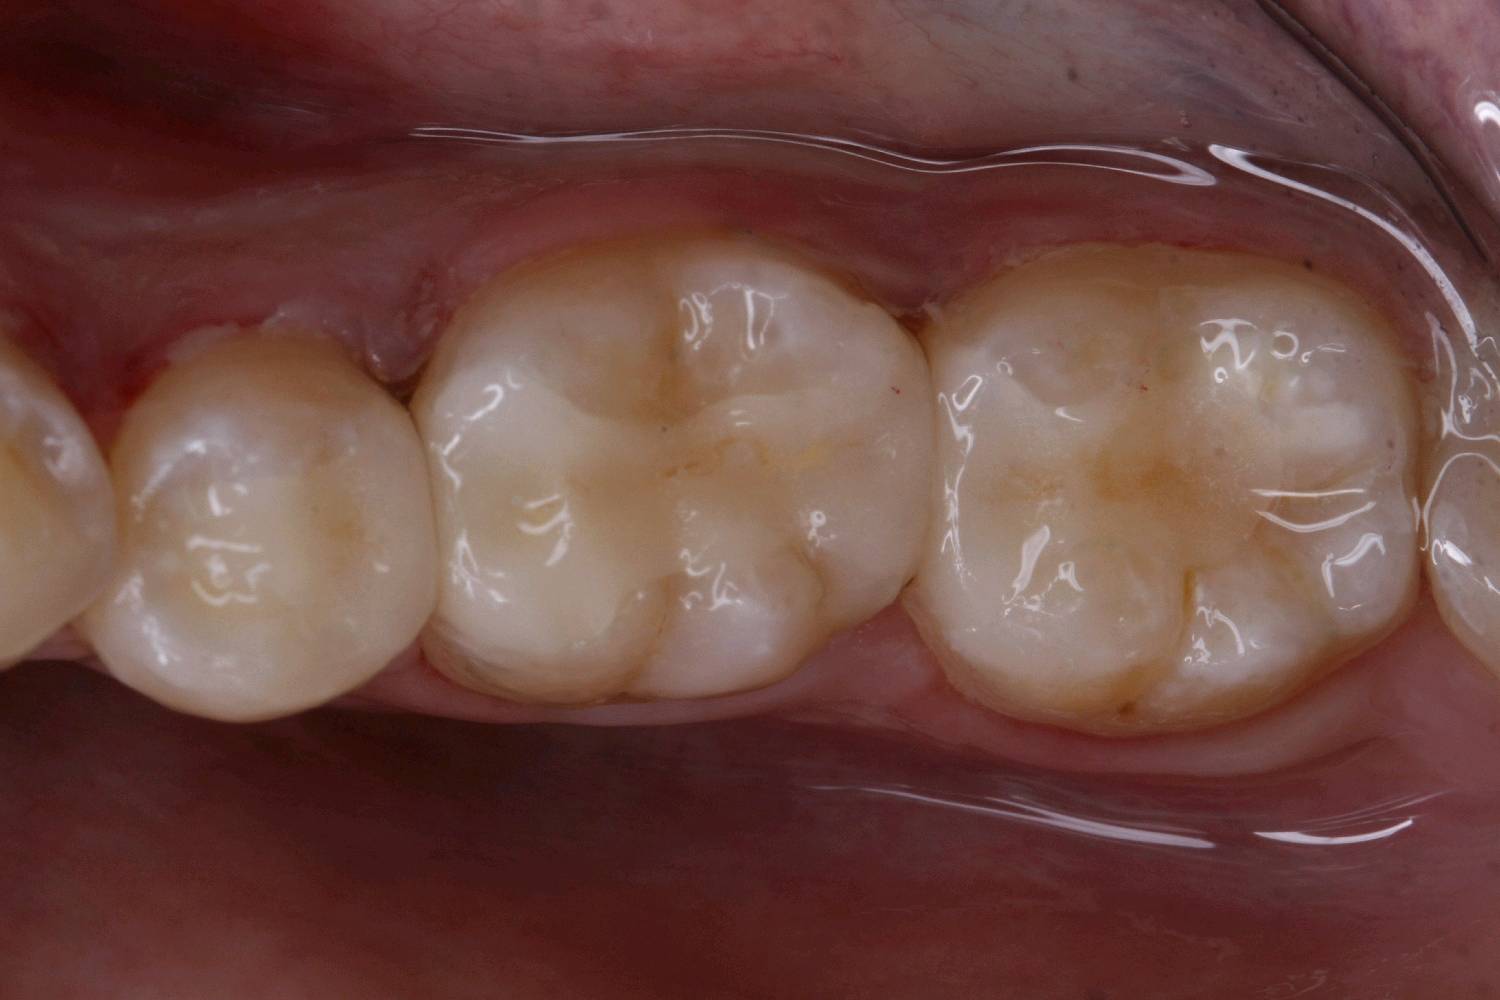

食物嵌塞为细菌提供了良好的滋生环境,容易导致细菌大量繁殖,产生酸性物质,从而增加蛀牙的风险。最好是用嵌体修复,能更好的恢复牙体的形态和功能。想要有一口好牙齿,做起来也不难。但是,单单口腔清洁这件小事,大多数人都没做好。你以为刷遍了牙齿的每个角落,但可能只刷了一半的牙。刷毛无法有效进入牙缝隙刷牙后仍有食物残渣等残留于牙齿邻面部位导致邻面龋坏。平时不易察觉,需要定期检查,为了更恢复邻接关系,预备制作嵌体,更好的恢复了牙体形态,增加了固位力,恢复正常的邻接关系,可以得到更好洁。基牙预备后,通过德国西诺德 CEREC ,当日完成即可佩戴,患者满意。